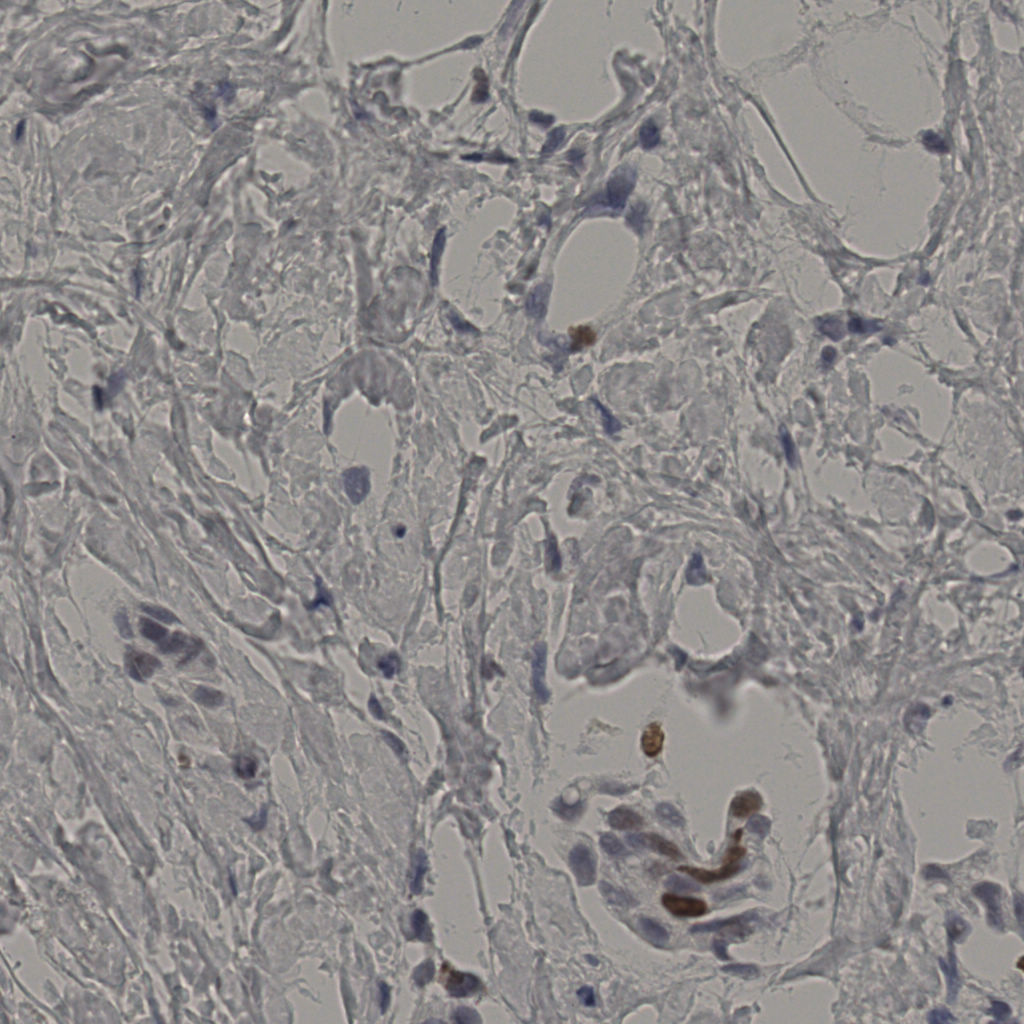

5.31%

Ki67 指数

阴 19502

阳 1093

标记后

标记前